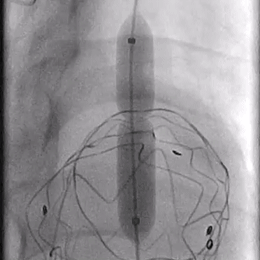

06. 沿右股动脉引入8F长鞘,置入8*50mm Viabahn覆膜支架于开窗处,远端避开左椎动脉,近端超过覆膜支架1cm并完成释放。

07. 最后行全主动脉造影示LSA开窗支架重建良好,近端主体支架定位显影良好,腹主动脉右肾动脉、腹腔干动脉及肠系膜上动脉显影较支架植入前明显改善。

术后1周复查主动脉CTA显示胸主动脉血管重塑良好,开窗支架形态正常。远端内脏区显影良好。